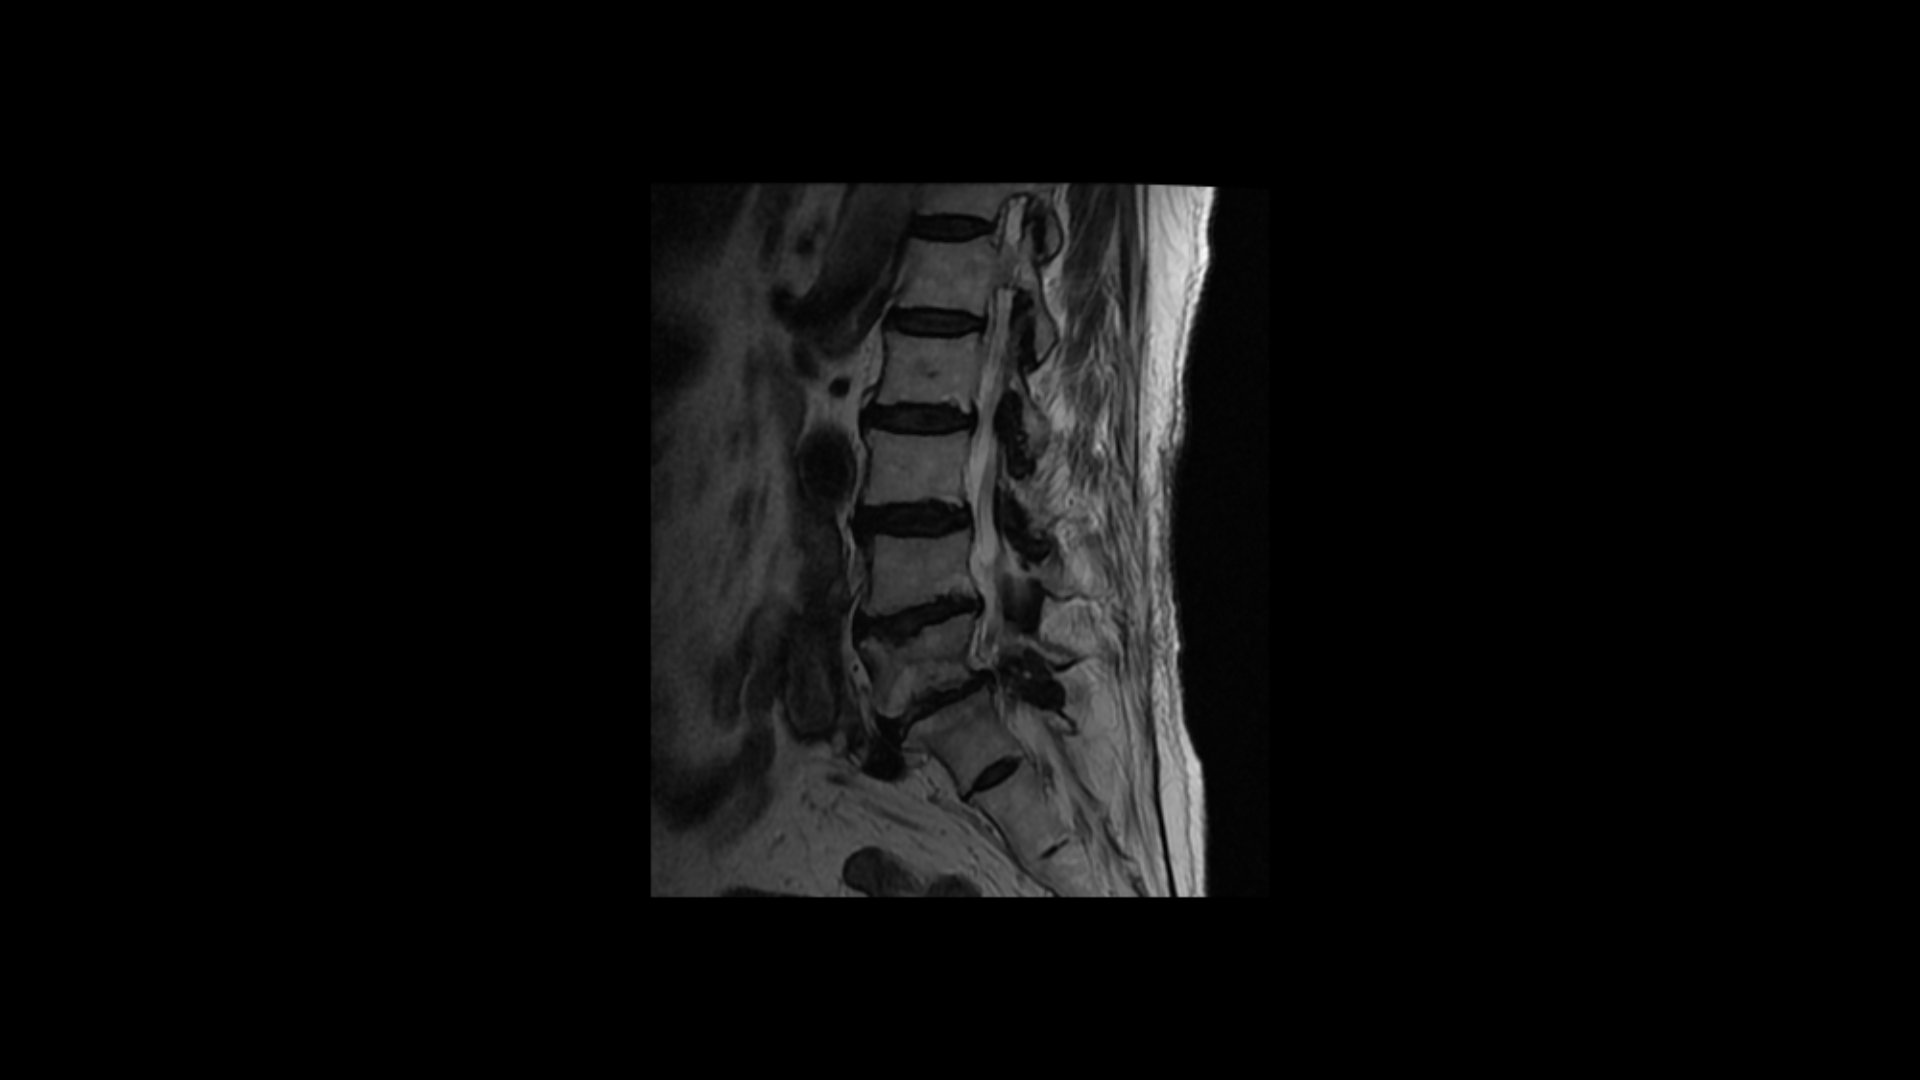

이분 MRI를 보면 퇴행성디스크가 여러 마디가 있고 그 중에서도 특히 5번 1번에는

전방전위증과 함께 2번의 수술로 인해 척추관 내부가 지저분해 보이고

또 오른쪽과 왼쪽으로 나가는 신경 구멍이 많이 좁아져 있습니다.